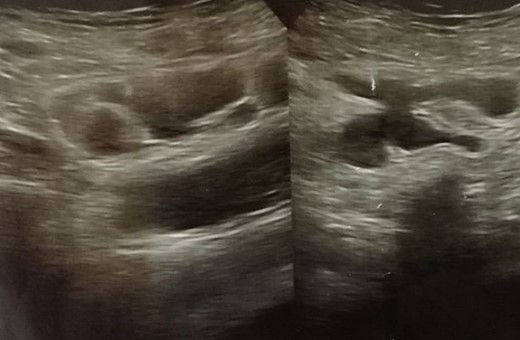

The laboratory hematology results revealed abnormalities such as, WBC (11.93 × 103 /μl), platelet (417 × 103/μl), TSH (5.87 IU/ml), total T3 (1.58 nmol/l), and total T4 (66.03 nmol/l). Her blood urea level was (28 mg. dl) and her serum creatinine level was (0.67 mg. dl). Abdominal sonography showed a normal uterus size, clear cavity, mildly bulky myometrium heterogeneous texture adenomyosis 6 mm posterior mural fibroid, normal endometrium, thickness 2 mm, and no cervical mass. A separated tubular fluid-filled structure was seen in the pelvis superior to the uterus, mainly on the right side; no obvious peristalsis could be seen within it during the examination, and the hydrosalpinx dilated the small bowel loops (ileum) (Fig. 1). For further investigation and clearer vision, magnetic resonance imaging (MRI) or computed tomography (CT) with oral contrast is recommended.